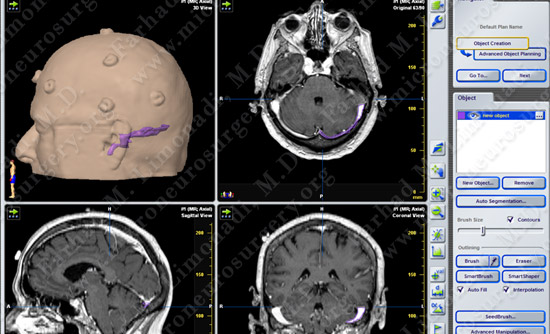

Imaging

- MRI scan of her brain demonstrated a vascular structure (red) impinging and compressing the trigeminal nerve (yellow) at root entry zone.

- Computer navigation and stereotaxy is also utilized